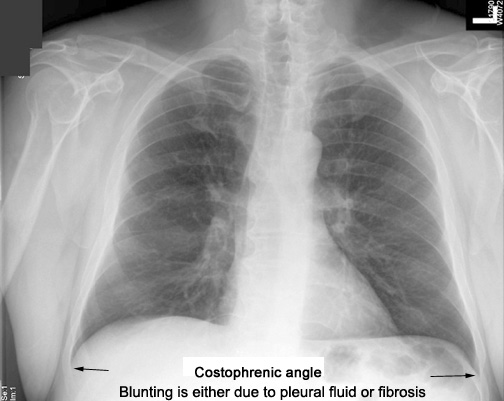

| CXR 8 | Identify costo diaphragmatic (costo phrenic) angles | What does blunting of costo diaphragmatic angle imply? | Answer |

| CXR | Identify costophrenic angles | What does blunting of costophrenic angle imply? | Answer |